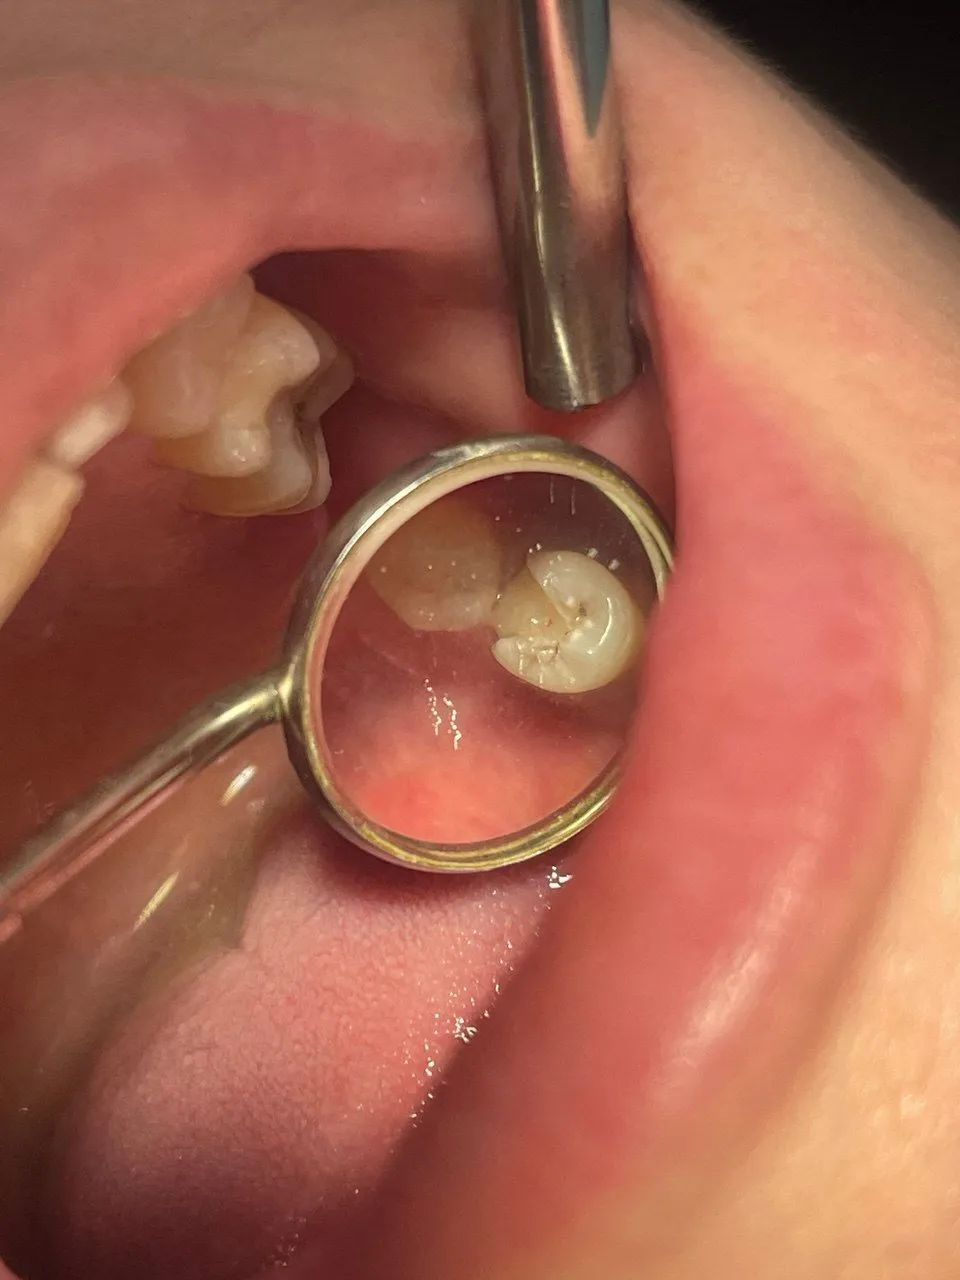

Пациентка, женщина 40 лет. Обратилась с жалобами при накусывании в течение недели. Ощущение выросшего зуба. При осмотре выявлена пломба с нарушением герметизации и кариозным процессом по всему периметру пломбы.

Проведено эндодонтическое лечение и вскрытие абсцесса за 2 посещения. Рекомендовано покрытие зуб коронкой